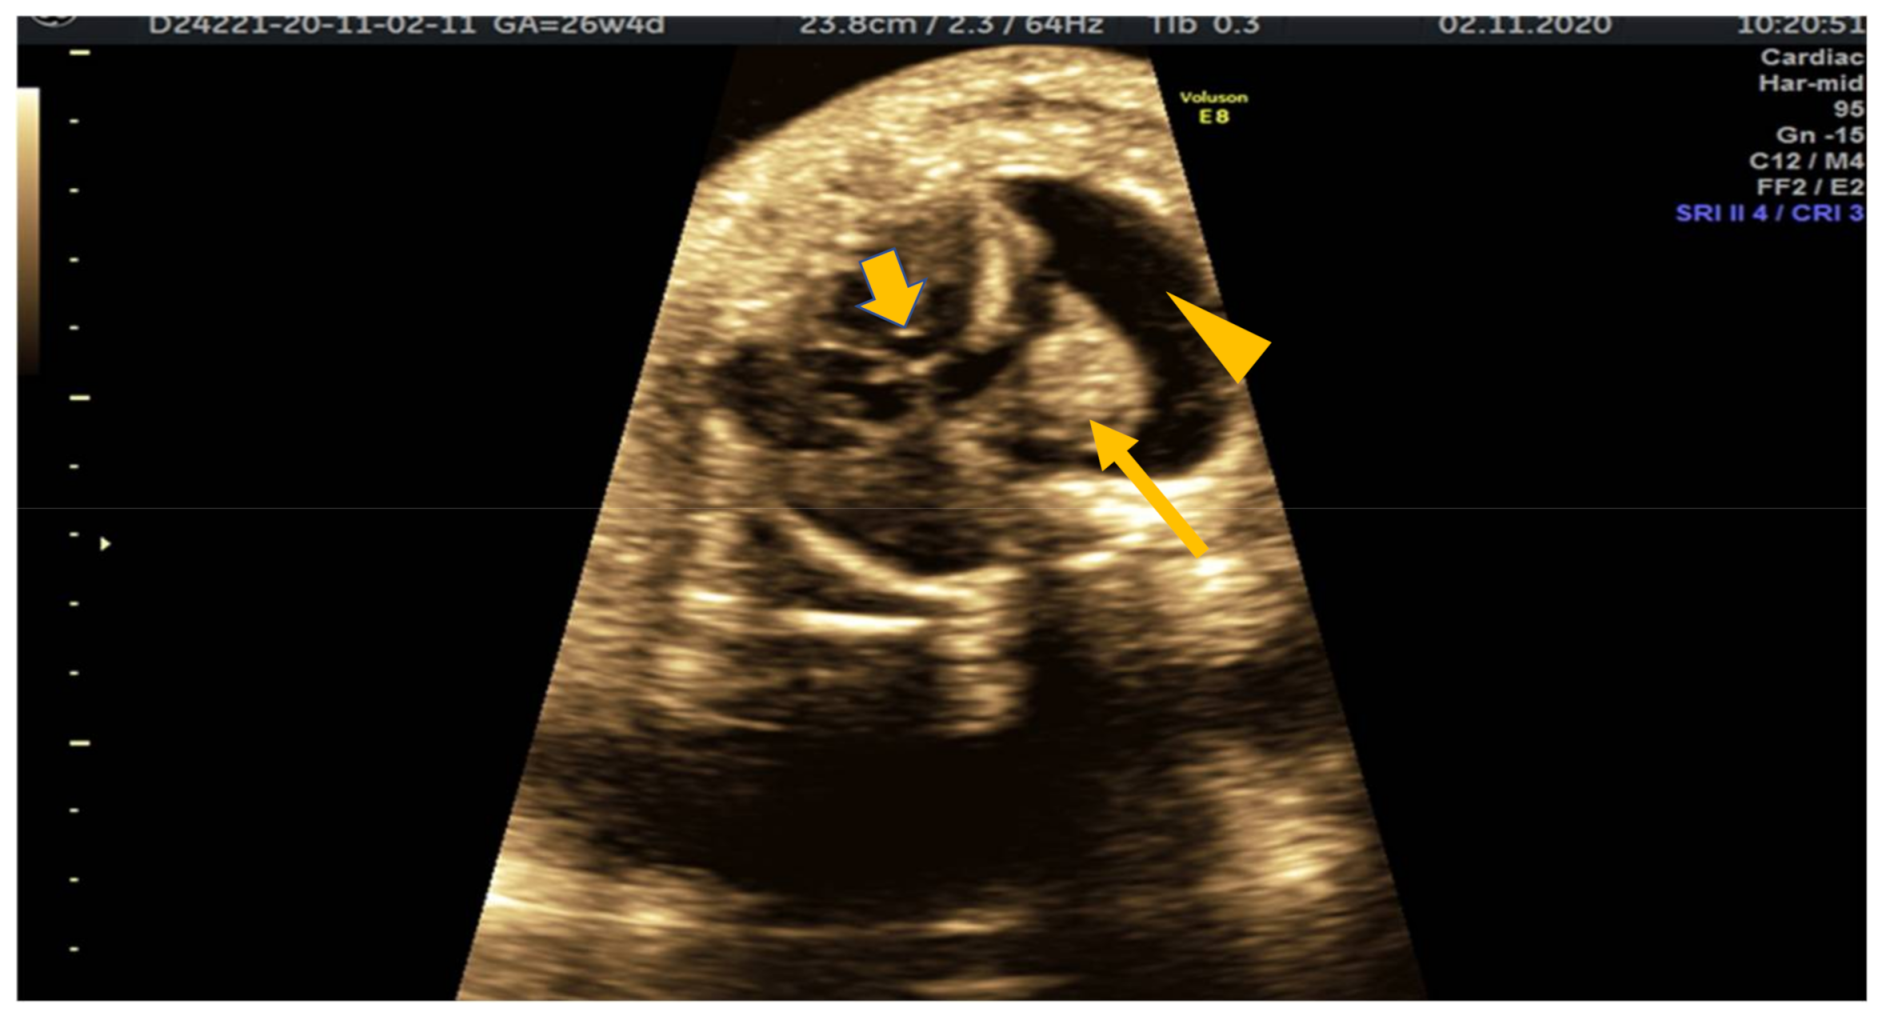

2. Case Presentation